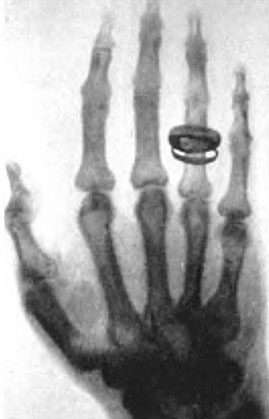

Иллюстрация к книге — Солнечное вещество и другие повести, а также Жизнь и судьба Матвея Бронштейна и Лидии Чуковской (сборник) [i_034.jpg]

Деревянная шкатулка с латунными гирьками, сфотографированная лучами Рентгена

Это один из первых снимков, сделанных самим Рентгеном.